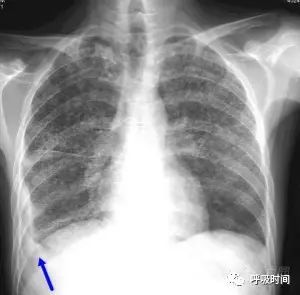

图片

图 12 粟粒影——急性血行播散性肺结核并右侧胸腔少量积液。双肺弥漫分布的粟粒影,呈典型的三均:大小均匀、分布均匀、密度均匀。右侧肋膈角变钝(蓝箭头)